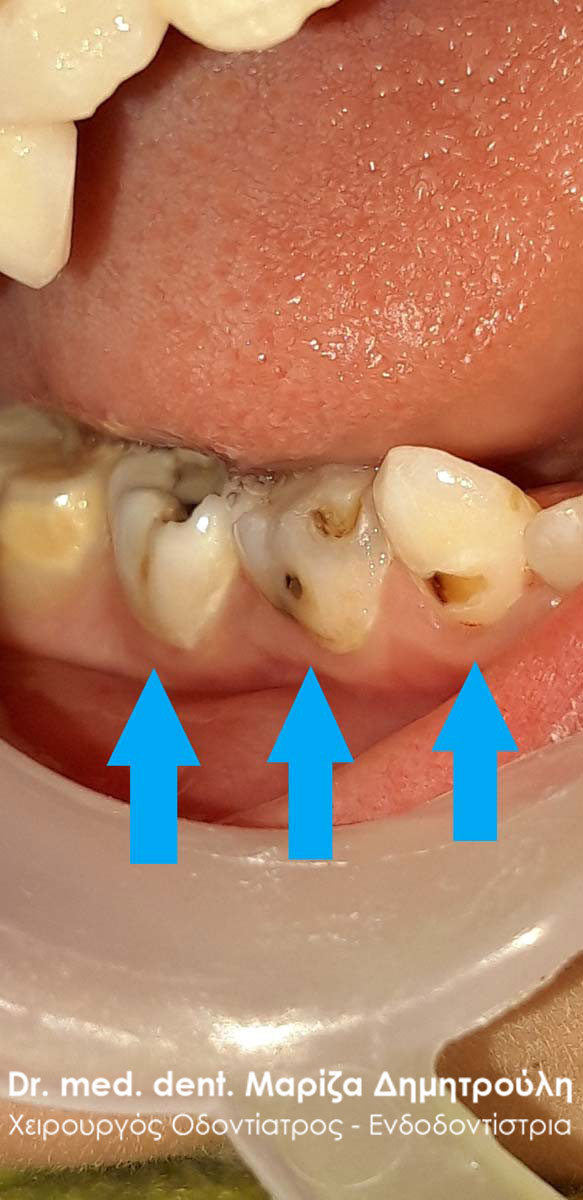

Περιστατικό – Αυχενικό σφράγισμα δοντιού

Σκοπός της ασθενούς ήταν τόσο η αισθητική όσο και η λειτουργική (η αθενής είχε ευαισθησία στα ψυχρά ροφήματα και τροφές) αποκατάσταση των αυχενικών αλλοίωσεων στους κάτω δεξιούς προγομφίους. Η αποκατάσταση πραγματοποιήθηκε με λευκά σφραγίσματα σύνθετης ρητίνης.

ΠΡΙΝ

META

Περιστατικό – Αυχενικό σφράγισμα δοντιού

Σκοπός της ασθενούς ήταν τόσο η αισθητική όσο και η λειτουργική (η αθενής είχε ευαισθησία στα ψυχρά ροφήματα και τροφές) αποκατάσταση των αυχενικών αλλοίωσεων στους κάτω δεξιούς προγομφίους. Η αποκατάσταση πραγματοποιήθηκε με λευκά σφραγίσματα σύνθετης ρητίνης.

ΠΡΙΝ

META